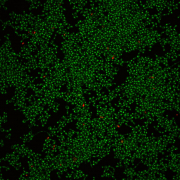

Confocal laser scanning microscopy shows that C. albicans develops biofilms on a plastic surface (left photo), and addition of purpurin suppresses biofilm formation (right photo). Green cells are living and red cells are dead.